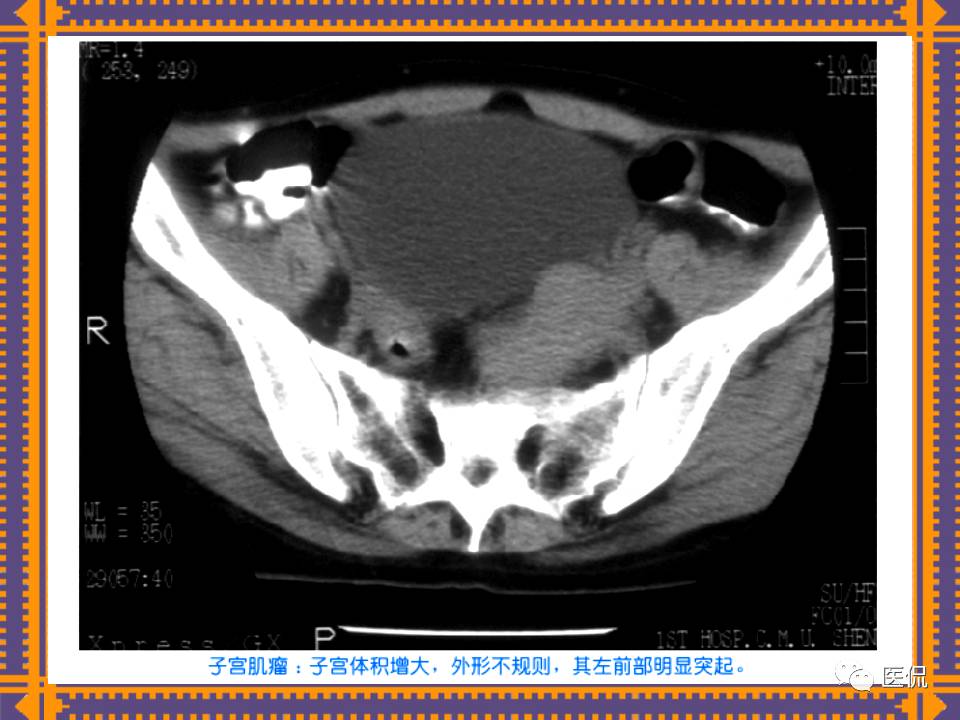

这篇PPT对男性生殖系统疾病:前列腺增生、前列腺癌;女性生殖系统疾病:子宫肌瘤、子宫癌、卵巢囊肿和卵巢肿瘤以及腹膜后间隙疾病进行了详细讲解。